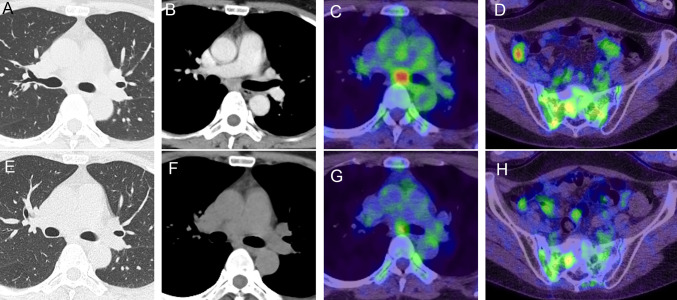

肺硬化性肺细胞瘤(PSP)是一种罕见的肺癌,偶尔表现为淋巴结和肺外转移,以及多发病变。转移性PSP的治疗方法尚不明确。本研究报告一名48岁女性病患,因左下叶单发结节手术后被诊断为PSP。四年后,复发发生在左肺门和纵隔淋巴结,需要进一步切除。同时,骶骨转移发生,需要姑息性放疗。遗传分析发现肿瘤中AKT1 E17K突变,PSP特征,缺乏程序性细胞死亡配体1 (PD-L1)表达。复发2年后,肿瘤复发于左乳腺及纵隔淋巴结。ipilimumab和nivolumab联合免疫治疗在这个转移性PSP病例中产生了显著的阳性反应。这是在各种局部治疗失败后,ipilimumab和nivolumab成功治疗多发性远处转移性PSP的第一例报道。需要进一步的病例序列来验证免疫治疗对转移性PSP的疗效。

Pulmonary sclerosing pneumocytoma (PSP) is a rare form of lung cancer that occasionally presents with lymph node and extrapulmonary metastases, and multiple lesions. The treatment of metastatic PSP remains undefined. This study reports the case of a 48-year-old female patient diagnosed with PSP following surgical intervention for a solitary nodule in the left lower lobe. Four years later, recurrence occurred in the left hilar and mediastinal lymph nodes, necessitating an additional resection. Concurrently, sacral metastases developed and required palliative radiotherapy. Genetic analysis identified an AKT1 E17K mutation, characteristic of PSP, and absence of programmed cell death ligand 1 (PD-L1) expression in the tumor. Two years post-recurrence, the tumor recurred in the left mammary gland and mediastinal lymph nodes. Combination immunotherapy with ipilimumab and nivolumab yielded a significantly positive response in this metastatic PSP case. This is the first reported case of successful treatment of multiple distant metastatic PSP with ipilimumab and nivolumab, following the failure of various local treatments. Further case series are warranted to validate the efficacy of immunotherapy in metastatic PSP.